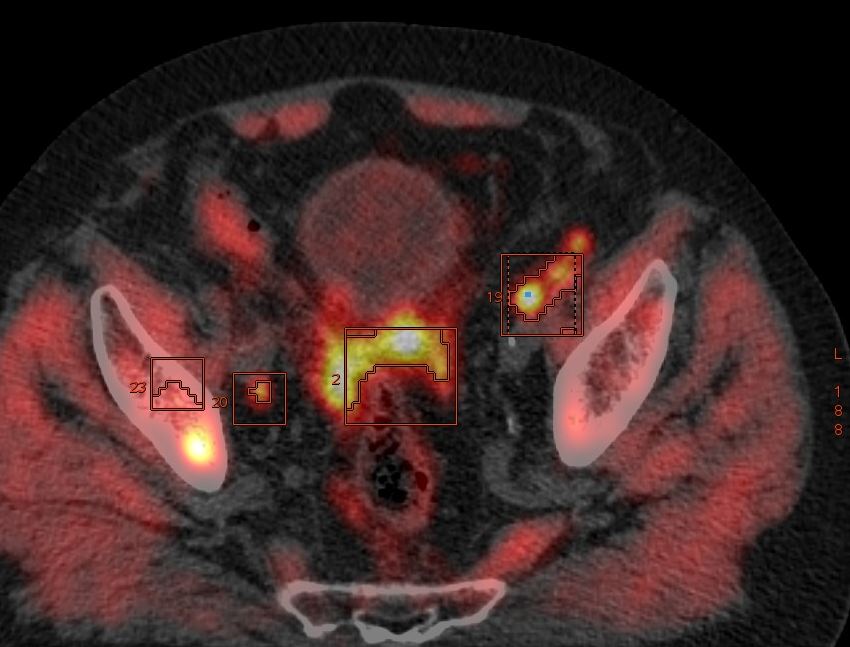

Acquisition réalisée 69 min après injection de 262,5 MBq de FLUOROCHOLINE et de 20 mg de LASILIX

L’examen permet de trouver une atteinte de la prostate dans sa globalité avec une extension aux vésicules séminales, à la paroi vésicale, une atteinte osseuse et ganglionnaire lombo-aortique très importante.

On visualise aussi une extension pelvienne vers le rectum avec de nombreux ganglions périrectaux.

On notera la présence très inhabituelle de nombreux nodules hyperfixants de carcinose pelvienne et abdominale. L’analyse de la littérature montre que cela reste très peu fréquent.